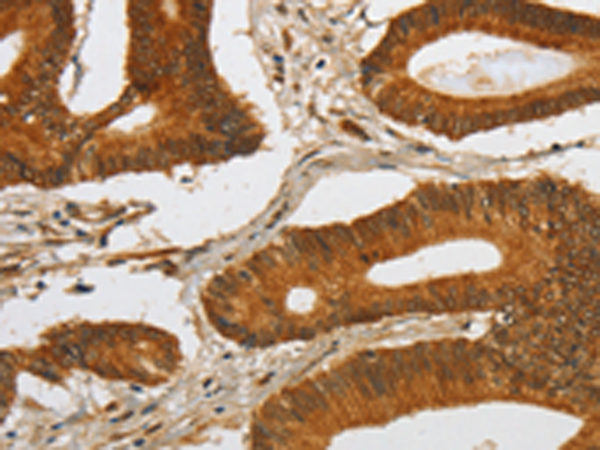

分类: 科研抗体货号: P08004别名: mATG9; APG9L1; MGD3208应用: WB,IHC反应种属: Human, Rat